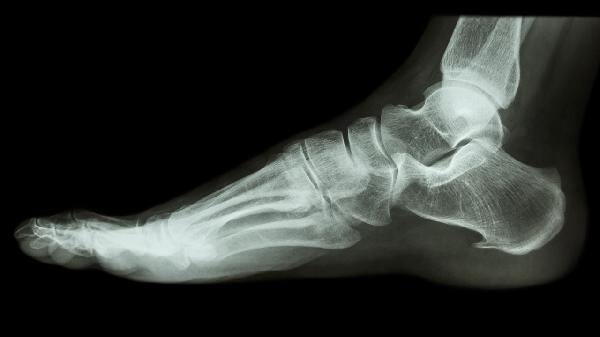

在医生允许后从部分负重开始过渡,初期使用拐杖分担体重。每周增加10%-15%负重比例,6-8周后逐步过渡到完全负重。需定期复查X线确认骨折愈合进度。